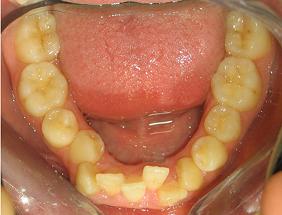

Con frecuencia ocurre que algunos dientes no están correctamente colocados. Esto puede producirse tempranamente por problemas de espacio en las arcadas dentales, es decir, el espacio disponible en las mismas es menor que el que necesitan los dientes. Como consecuencia se produce lo que se conoce como apiñamiento. También la presencia de hábitos en la edad infantil puede tener efectos similares.

Con el tiempo, y especialmente si entre los dientes y las articulaciones mandibulares no existe una buena armonía, es decir, si el máximo cierre dental no coincide con las articulaciones en su correcta posición, esto puede hacer que se produzcan algunos movimientos dentales, especialmente en incisivos, tanto inferiores como superiores.

Si las bases esqueléticas sobre las que se sitúan los dientes, no están correctamente relacionadas entre sí, lógicamente esto también afectará a la posición de los dientes y a la relación de las dos arcadas dentales.